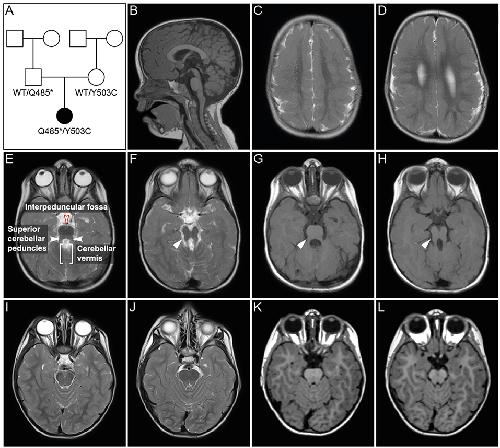

The Frog Xenopus as a Model to Study Joubert Syndrome: The Case of a Human Patient With Compound Heterozygous Variants in PIBF1., Ott T, Kaufmann L, Granzow M, Hinderhofer K, Bartram CR, Theiß S, Seitz A, Paramasivam N, Schulz A, Moog U, Blum M, Evers CM., Front Physiol. January 1, 2019; 10 134. |